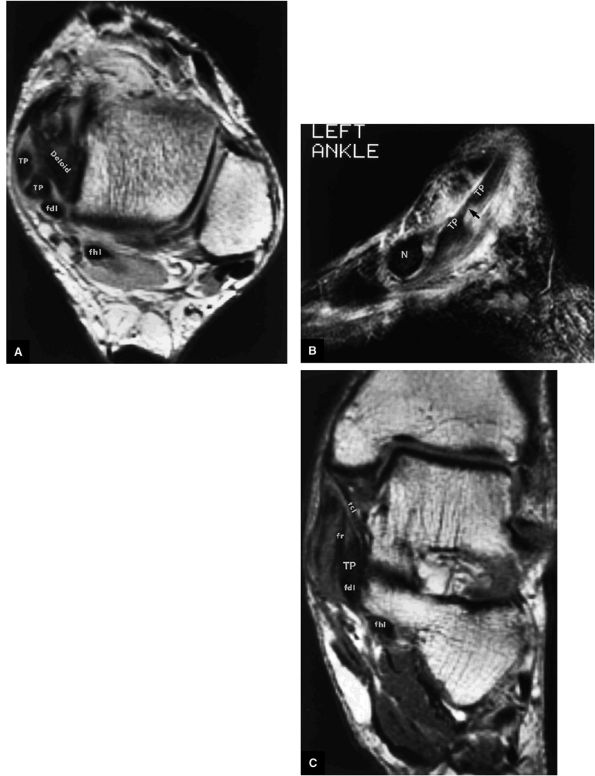

FIGURE 5.133 ● (A) A T1-weighted axial image depicting a longitudinal rupture of the tibialis posterior tendon resulting in two subtendons of the tibialis posterior (TP) at the level of the medial malleolus and deltoid ligament. Note that this split creates the appearance of four separate medial tendons. The two anterior medial tendons represent the anterior and posterior half of the tibialis posterior. (B) A T2*-weighted sagittal image identifies the attenuated portion of the tibialis posterior at the longitudinal tear site (arrow). (C) The relationship of the tibialis posterior (TP) to the adjacent medial structures on a corresponding T1-weighted coronal image. fdl, flexor digitorum longus tendon; fhl, flexor hallucis longus tendon; N, navicular bone; tcl, tibiocalcaneal ligament; fr, flexor retinaculum.